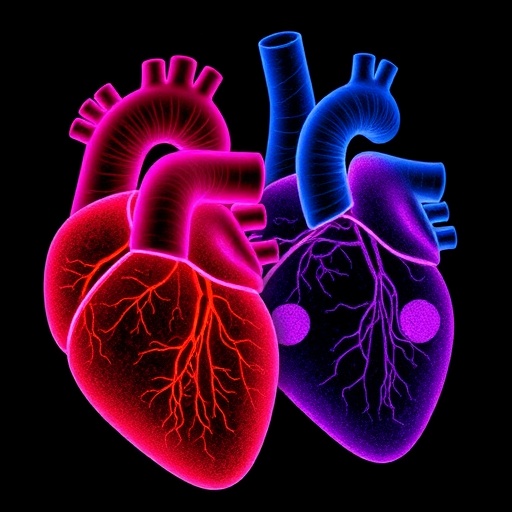

Left and Right Ventricles Show Different Resilience to Cardiac Arrest Effects

A groundbreaking study spearheaded by researchers at the Centro Nacional de Investigaciones Cardiovasculares Carlos III (CNIC) unveils critical new knowledge...